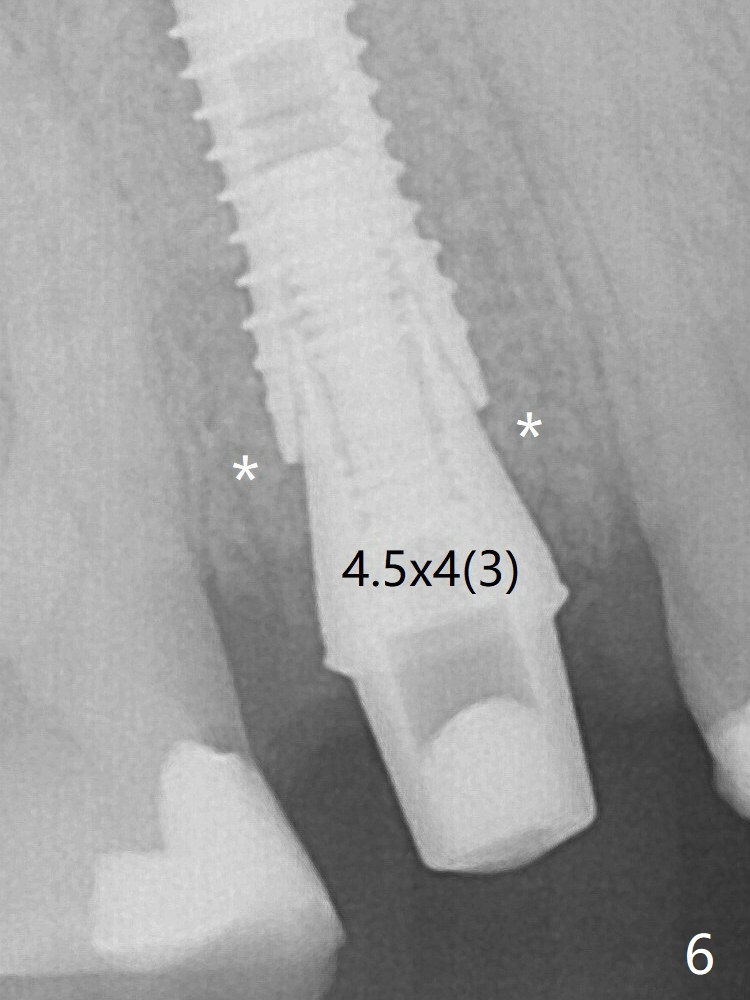

A 3.8x18 mm (definitive) implant is placed with <40 Ncm with the implant plateau apical to the lingual crest (Fig.4 (dashed line: upper border of the buccal defect)). The buccal plate defect is repaired by Vanilla Graft (Fig.6 *) before and after insertion of a 4.5x4(3) mm abutment. The buccal plate defect seems to being repaired 4 months postop (Fig.7).